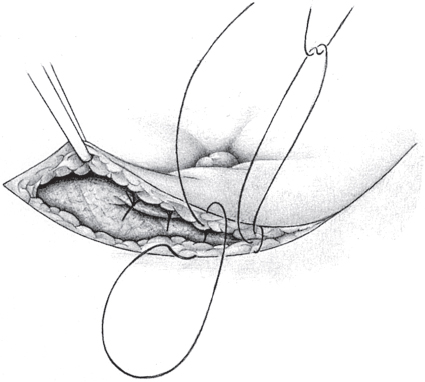

When the hernia is indirect, the sac is treated and the femoral compartment is then explored digitally through the expanded deep inguinal ring (

Fig. 3.1).

Sutured repair, e.g., by the Shouldice method (see section

2.2.2.4), can then be carried out, especially in younger patients. Unlike in men, the deep inguinal ring is closed completely. The proximal stump of the round ligament can be included in the lateral part of the Shouldice suture (

Fig. 3.2).